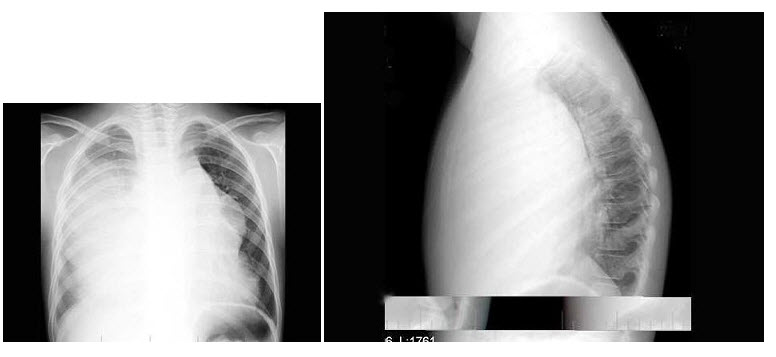

148、单项选择题

女,65岁,腰背部疼痛,僵硬半年余,结合影像学检查,最可能的诊断是()

A.脊椎肿瘤

B.椎体压缩性骨折

C.化脓性脊柱炎

D.强直性脊柱炎

E.脊椎退行性变